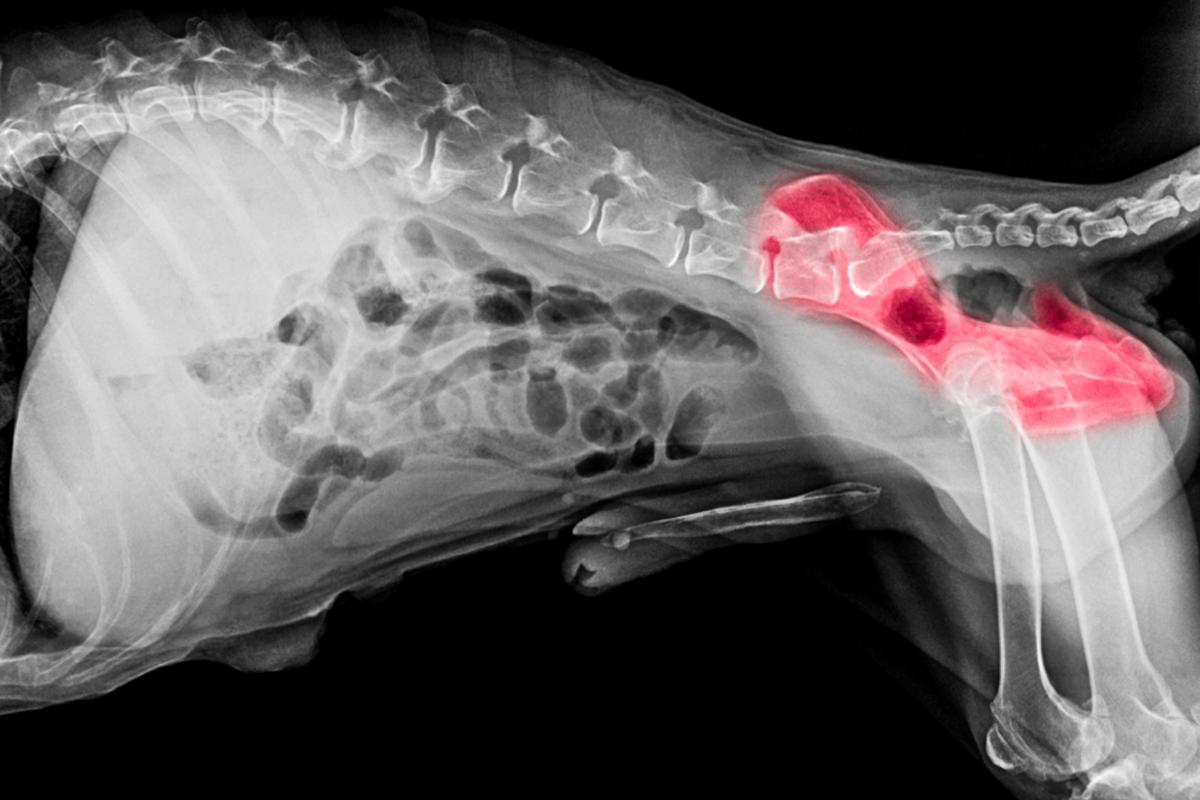

Displasia de cadera

Es una de las causas principales que dan respuesta a tu pregunta de por qué a tu perro mayor le fallan las patas traseras. Es típica en perros grandes y suele ser hereditaria. Es frecuente en canes de edad avanzada, pero también puede producirse en perros jóvenes.

En la displasia de cadera, el acetábulo (hueco en el hueso de la pelvis que aloja la cabeza del fémur) y la cabeza del fémur se van deformando hasta que la cabeza entra y sale del acetábulo. Esto produce dolor y cojera.

Tratamiento

El tratamiento de la displasia de cadera pasa por la administración de condroprotectores y AINEs, así como del uso de un soporte de cadera y la prevención de la obesidad.

Existe cirugía preventiva que puede considerarse en cachorros de razas predispuestas, como el pastor alemán, para que no aparezca con el paso de los años. Conoce todos los detalles en este post: "Displasia de cadera en perros - Síntomas y tratamiento".